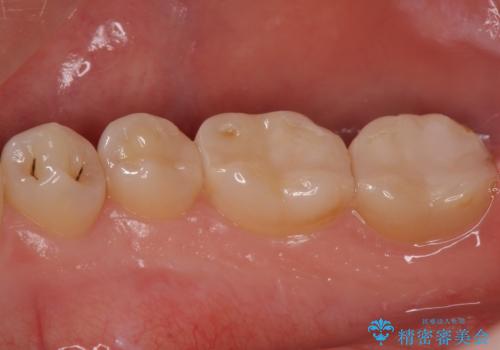

- 右下567 セラミックインレー 77,000円×3本費用は治療当時の料金となります

写真でもレントゲン画像でも確認できるように、段差がなく適合の良い詰め物を装着することができました。